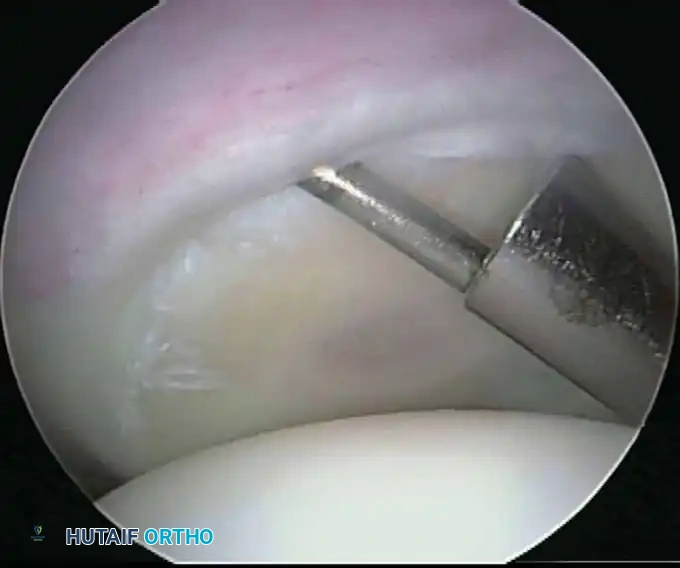

Electrocautery and Radiofrequency Ablation

In addition to hydrostatic pressure, active hemostasis is achieved using arthroscopic electrocautery or bipolar radiofrequency (RF) ablation devices. These wands are indispensable for coagulating bleeding vessels in the subacromial bursa, releasing the coracoacromial ligament, and meticulously preparing the footprint for rotator cuff repair without obscuring the visual field with hemorrhage.

Furthermore, the addition of epinephrine (typically 1 mg per 3 liters of irrigation fluid) induces local vasoconstriction, significantly reducing capillary oozing. When combined with controlled hypotensive anesthesia (maintaining mean arterial pressure between 70-80 mm Hg), the surgeon is afforded a pristine, bloodless field, allowing for the precise execution of complex knot-tying and tissue mobilization.